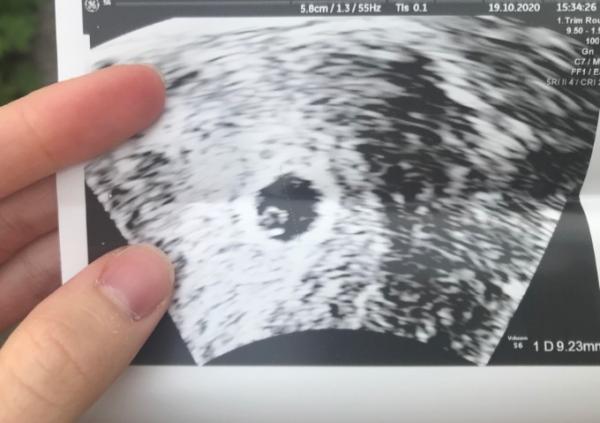

Hallo, dass tut mir mega leid , ich kenn mich da leider nicht aus aber ich kann dir mein US bild als vergleich anbieten war da auch sowas 5+4 herum ... was für schmerzen hast du den leicht ? Liebe Grüße...

Bild zu